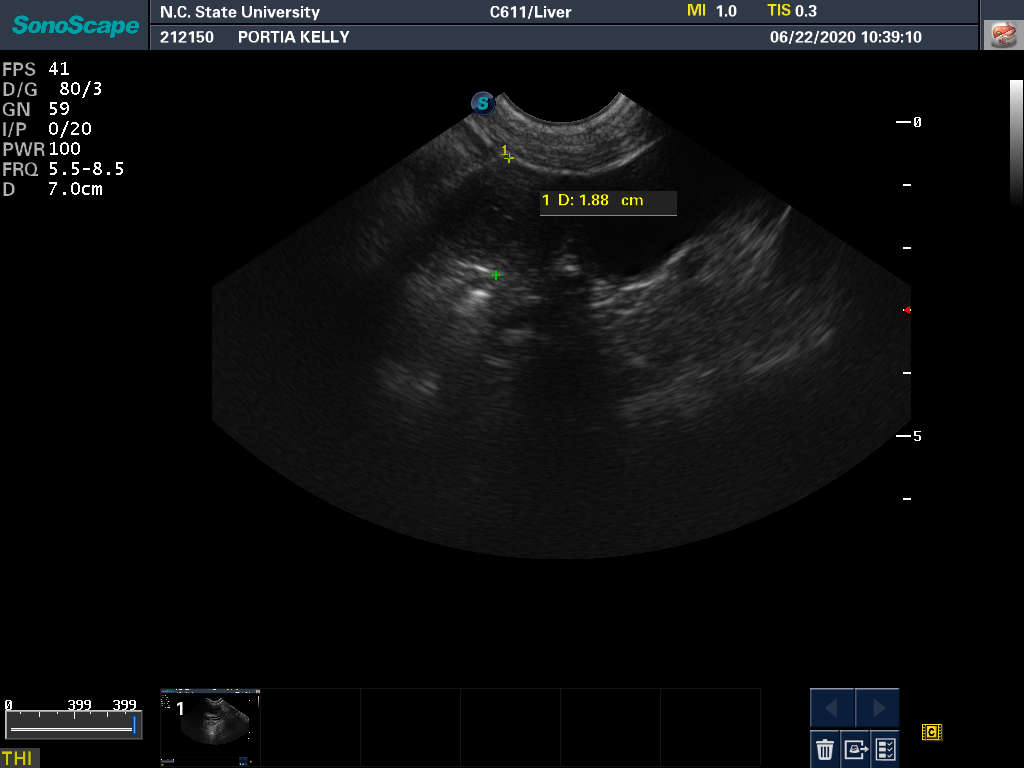

22 Jun

Ultrasound today by the theriogenology (reproduction) vets at NC State University showed the Portia is pregnant with most likely one puppy. It can be difficult to accurately count puppies using ultrasound - so there could be more than one puppy - but there is at least one puppy with a good heart beat.

The bad news is that the ultrasound also revealed an absorption site. Dogs absorb, rather than have miscarriages. So my repro vets are treating this as a "problem" pregnancy. Portia has been put on the drug terbutaline to "calm her uterus". We will be coming back to NC State for repeated ultasounds on a regular basis during the pregnancy.